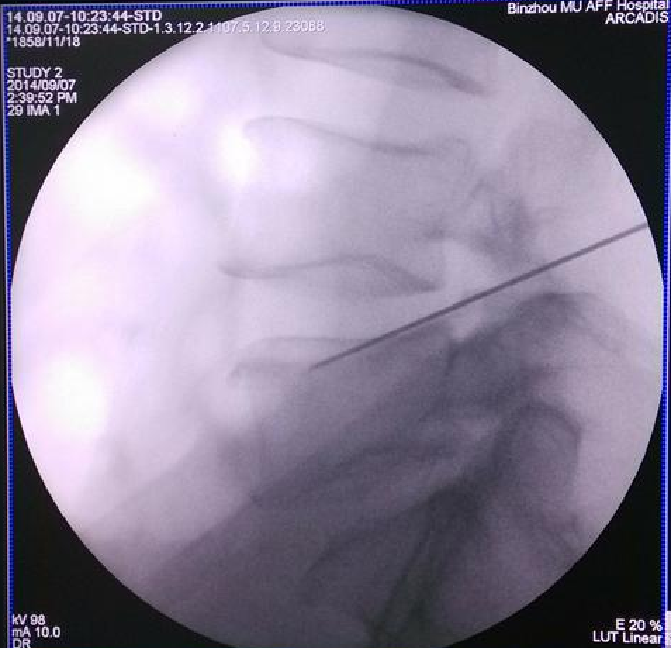

体表定位(C型臂下影像)

放置导丝(扩张软组织)用锋利的小手术刀在进针点皮肤切开一个大约8 mm的切口。沿着导丝向小关节方向插入导杆。在导杆外沿着导杆逐级放套管向外扩张软组织。

扩椎间孔骨钻套在套管的外边。沿着套管放置骨钻,去掉小关节远端增生的骨质,扩大椎间孔。

使用骨钻时,用C型臂从前后和侧面确定器械和骨钻顶端的位置。骨钻的最前端不能超过中线,以避免刺激或损伤神经。

用C型臂确定工作套管放置的位置。正确的位置应该是放在神经根下方,椎间盘水平,顶端正好在中线,开口朝向突出的髓核。